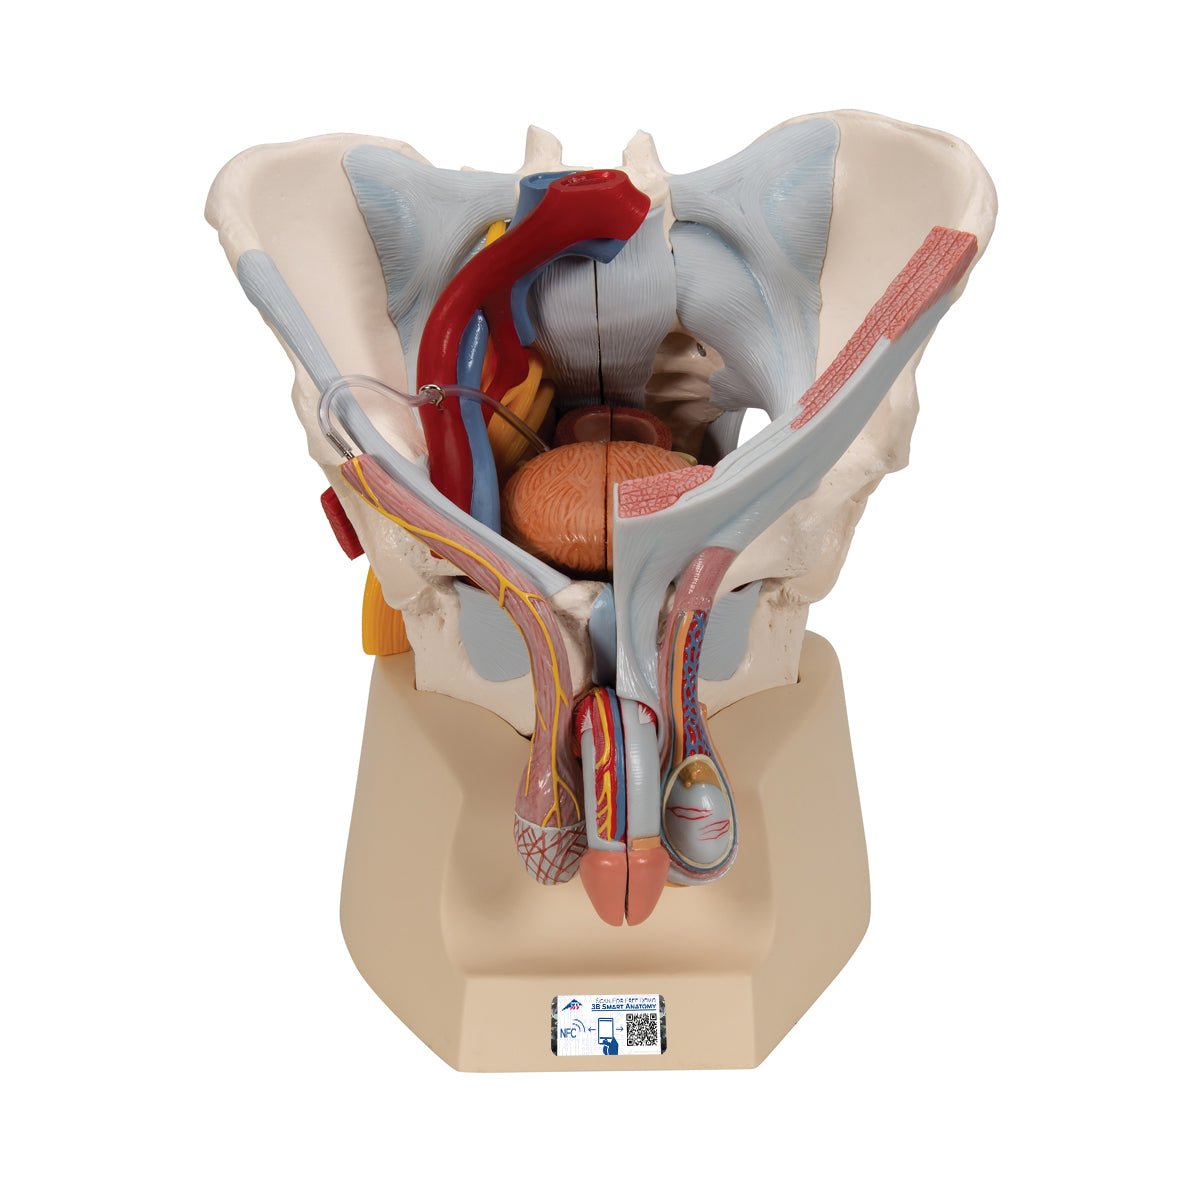

51IYtrJhcDL._AC_UF894,, Amazon.com: HZHXIFUF Anatomy Model 30Inch Male Anatomy,

Amazon.com: HZHXIFUF Anatomy Model 30Inch Male Anatomy, Amazon.com: DOC.ROYAL Male Human Anatomical Model Art,

Amazon.com: DOC.ROYAL Male Human Anatomical Model Art, Male pelvis with ligaments, pelvic floor and organs, 7-parts,

Male pelvis with ligaments, pelvic floor and organs, 7-parts,【中古】[PTM]プレミアムバンダイ限定 Figure-rise Standard Amplified(フィギュアライズ スタンダード アンプリファイド) メタルガルルモ